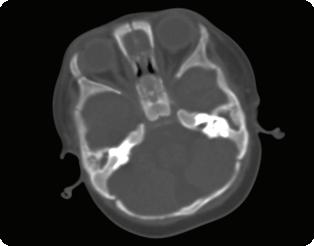

ЧМН - интактни. Запазена зенична реакция. Това наложи нови изслед -

вания и консултации с УНГ специа -

лист с оглед доказания двустранен мастоидит.

Осъществен контролен КАТ на глава: не се скенират инфилтративни лезии в мозъчния паренхим.